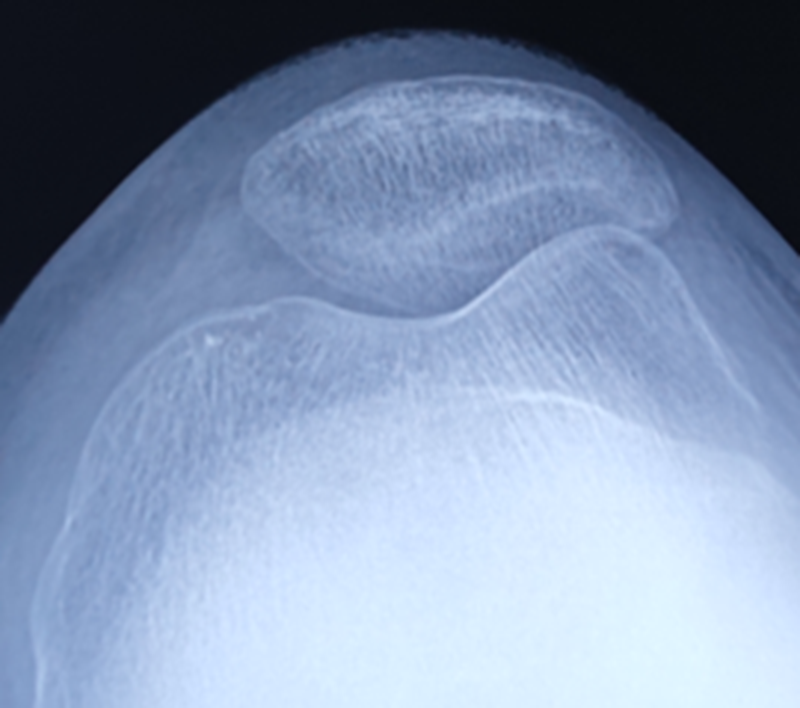

术前X线

术前MRI